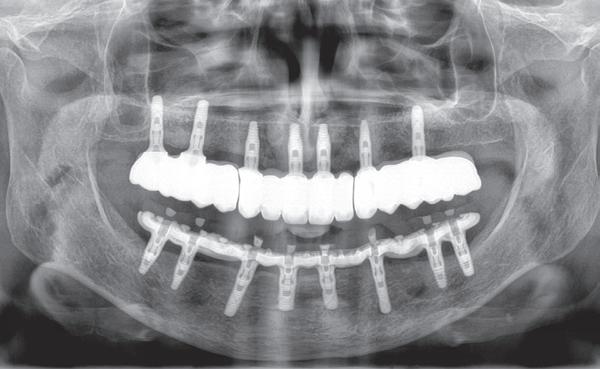

5. Implantaten geplaatst op geleide van een boorsjabloon; botopbouw met sinuslift volgens de GBR-techniek en Caldwell Luc methode; materialen: Oragraft & BioOss, Ossix membr, hyaluronzuur. In de BK is gekozen voor Bego implantaten (Bego SC en RSX 3,75x 11,5 & 13mm).

6. In het front zijn Bego 3,25mm

Tijdens de chirurgische behandeling worden na het afschuiven van de flap de posities bepaald van de implantaten met de boorsjabloon. In de bovenkaak worden 7 implantaten geplaatst en in de onderkaak 8

implantaten geplaatst terwijl in de zijdelingse delen voor een bredere diameter (3,75 & 4,1) is gekozen, met lengte 8,5 en 10mm.

7. OPT na abutmentchirurgie 6 maanden later. De integratie van de implantaten met de botopbouw & sinusliften verloopt voorspoedig.

(zie foto’s chirurgie en OPT’s). Gekozen is voor Bego SC & RSX Pro van een relatief smalle diameter (3,253,75). Alleen in de molaarstreek valt de keuze op een 4,1 mm in diameter. De lengte varieert tussen 8,5 en 13 mm afhankelijk van de ligging van de nervus alveolaris inferior en het foramen mentale als de neusbodem en de sinusholte. De keuze van de diameter wordt mede bepaald door de breedte van de processus ondanks de uit te voeren laterale botopbouw. Indien mogelijk gaat de voorkeur uit naar het plaatsen van implantaten in autoloog en daarmee vitaal bot.

Lateraal van de implantaten wordt de kaak fors uitgebouwd volgens de Hybride GBR-techniek met Oragraft (allograft) van Lifenet die wordt vermengd tot een cocktail met BioOss (xenograft) van Geistlich, autoloog geoogste botsnippers en verzameld bloed uit het wondgebied. De botgraft wordt bedekt met een Ossix (crossed linked) membraan en met Hyadent (hyaluronzuur) overspoten. De sinuslift wordt gelijktijdig met de laterale botopbouw volgens de Caldwell Luc methode uitgevoerd en de uitgeprepareerde holte opgevuld met de botgraft. De flaps worden eerst horizontaal ontlast (gemobiliseerd) en vervolgens naar elkaar toe gehecht met vicryl rapide. Daarbij wordt gebruikgemaakt van horizontale matrassen, zodat de wondranden passief tegen elkaar